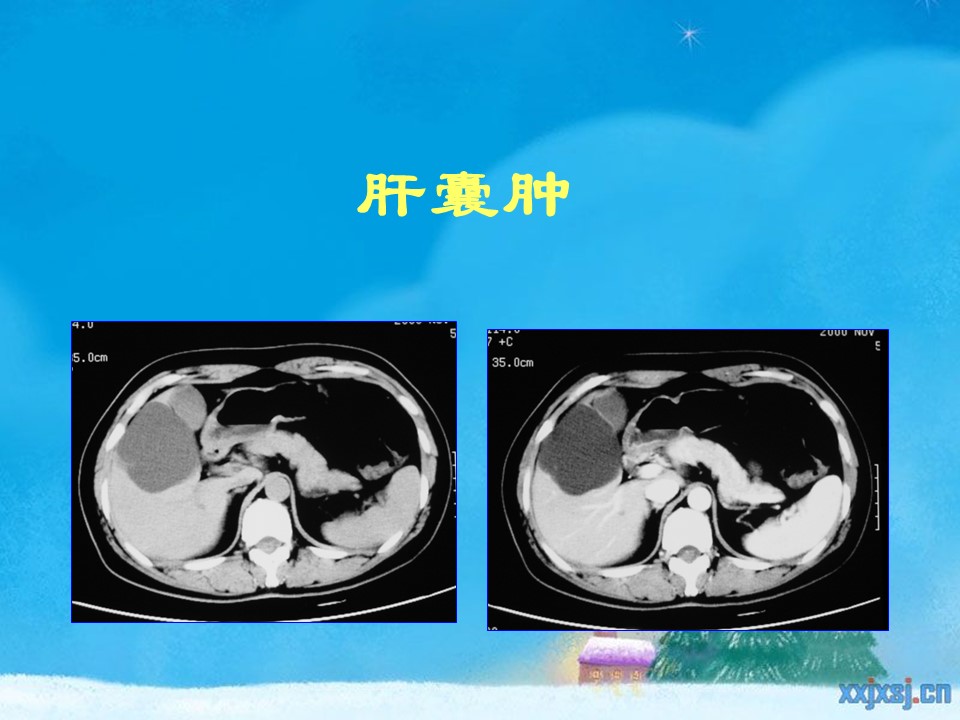

“腹部、盆腔影像诊断学PPT” 的相关文章